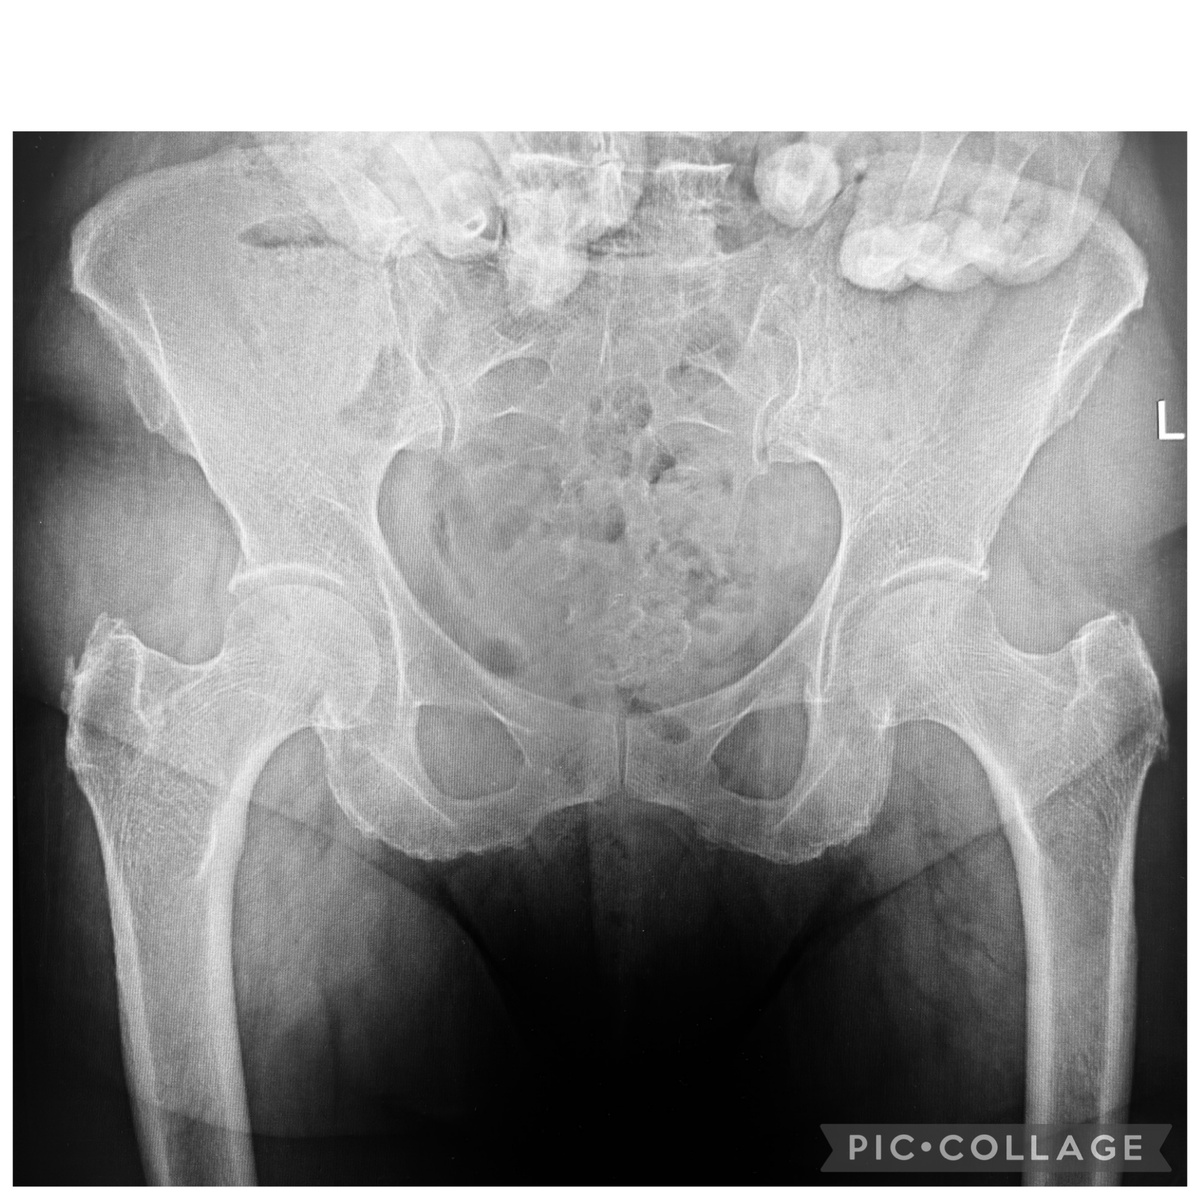

Довольно частая история: болит тазобедренный сустав. Во время ходьбы, после ходьбы… Вдруг, в течение года ни с того, ни с сего… Люди делают рентген (как в начале статьи), а там - ничего. Точнее, как обычно пишут рентгенологи, двусторонний коксартроз 1-2 ст. То есть, ничего выдающегося, просто суставами давно пользуются. Но болит-то один! Кстати, на этом фото действительно не видно, какой именно,

Довольно частая история: болит тазобедренный сустав. Во время ходьбы, после ходьбы… Вдруг, в течение года ни с того, ни с сего… Люди делают рентген (как в начале статьи), а там - ничего. Точнее, как обычно пишут рентгенологи, двусторонний коксартроз 1-2 ст. То есть, ничего выдающегося, просто суставами давно пользуются. Но болит-то один! Кстати, на этом фото действительно не видно, какой именно, можно только гадать.